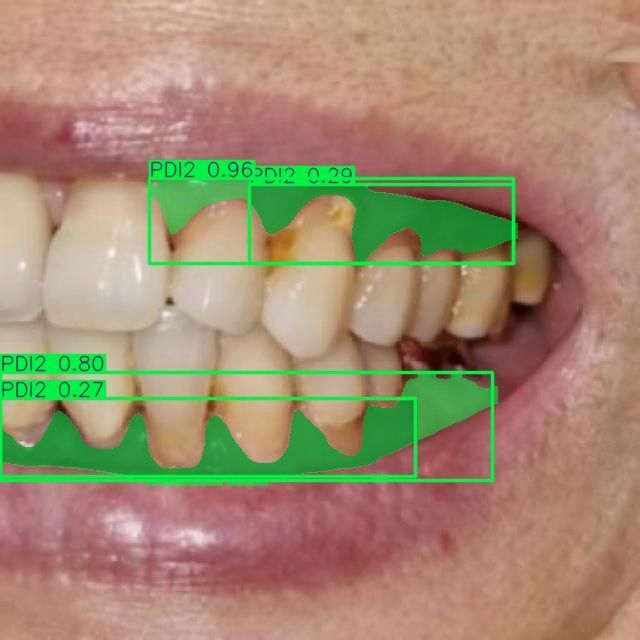

Мы проводим discovery-фазу для нашего клиента (стоматологическая клиника в Москве) и создали работающий прототип ИИ-сервиса, который автоматически сегментирует зубы и связанные патологии по 10 специализированным классам на стоматологических изображениях. Решение построено на Ultralytics YOLOv11-seg, обучено на пользовательском датасете и ускоряется на GPU (CUDA). Прототип уже демонстрирует корректную сегментацию и классификацию по классам кариеса, состояниям десен и показателям пародонта, что открывает путь к автоматизированной диагностике, системам поддержки клинических решений и оценке состояния зубов в реальном времени.

- Пародонтальные индексы: PDI1, PDI2, PDI3